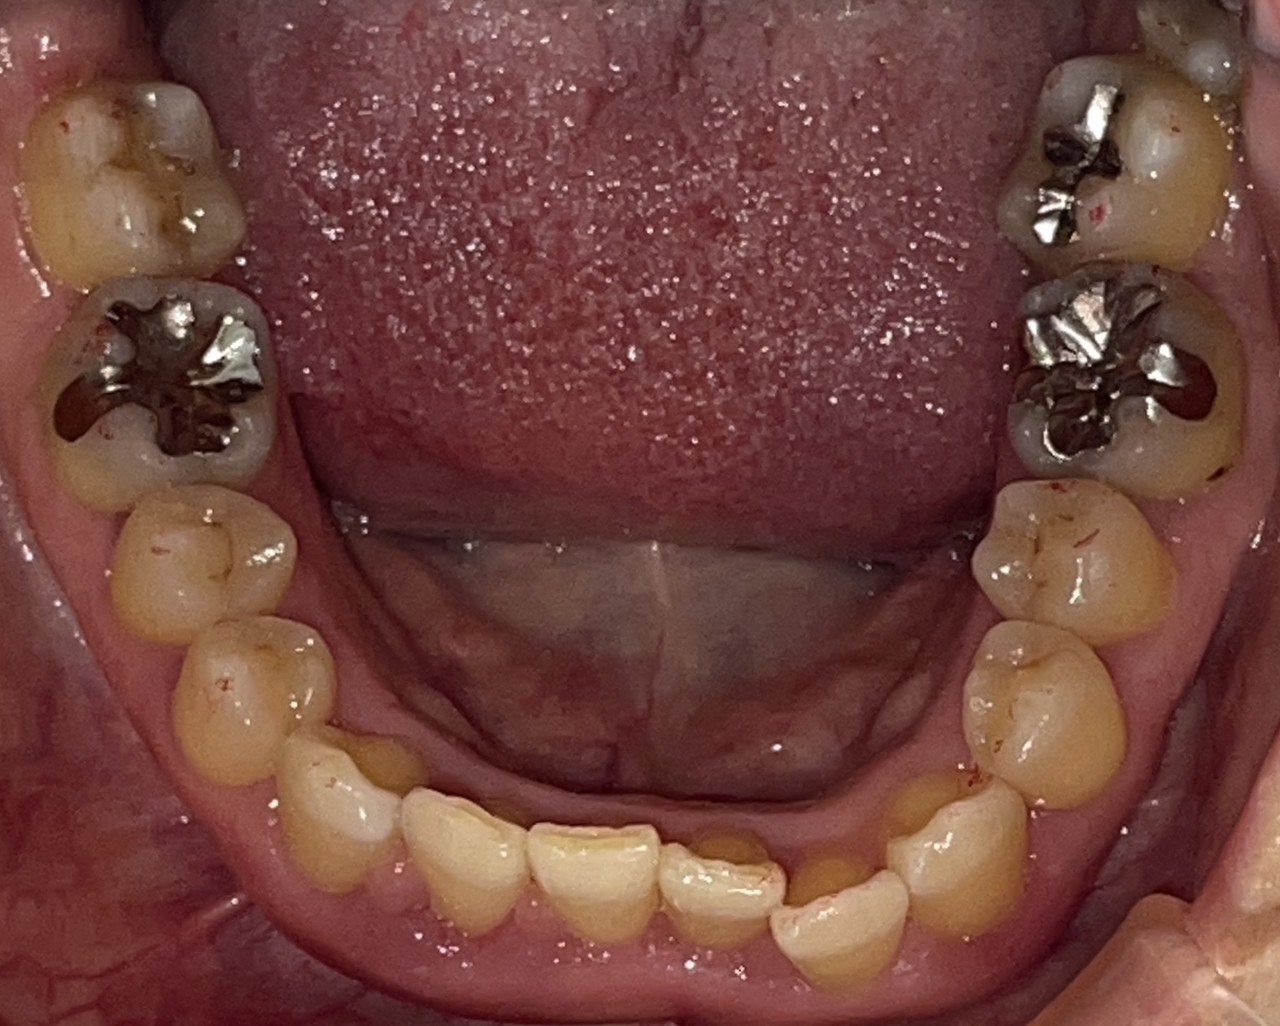

Before

After

矯正の種類 / SmileTRU

年齢・性別 / 10代女性

主訴  /  上顎前歯部が曲がっている(捻転症例)

治療期間 / 8ヶ月

費用 / 模型・3Dデータ診断 35,000円(税別) 上顎のみマウスピース14枚 308,000円(税別)

※マウスピース交換時別途調節料3,000円(税別)

副作用 / 口内炎・歯の移動に伴う痛み・知覚過敏 ※数日で収まる場合が多いです

リスク / 後戻り防止の為、夜のみマウスピースで保定を指示